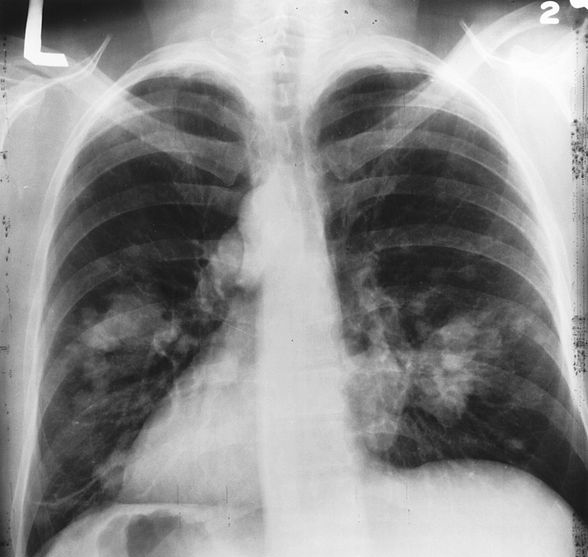

X-ray image of chest with possible lung cancer growth on the left side of the lung.